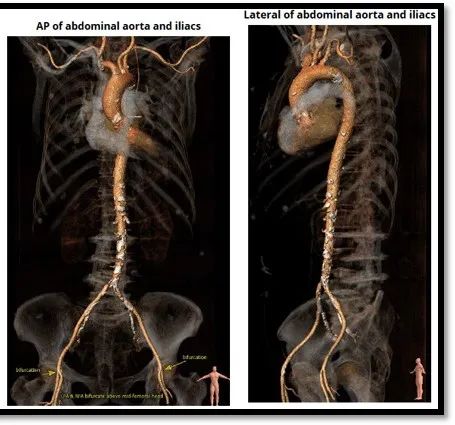

对入路血管分析发现,双侧股动脉分叉位置较高,右侧髂动脉最小管腔直径4mm,可疑斑块或血栓,左侧髂动脉最小管腔直径5.5mm。

难点二:患者双侧髂-股动脉多发动脉硬化斑块,伴有管腔细小、血管严重迂曲及重度钙化,右侧入路最小直径4mm,左侧入路最小直径5.5mm,多次尝试均难以通过,最终应用Inline sheath技术成功将瓣膜送达;